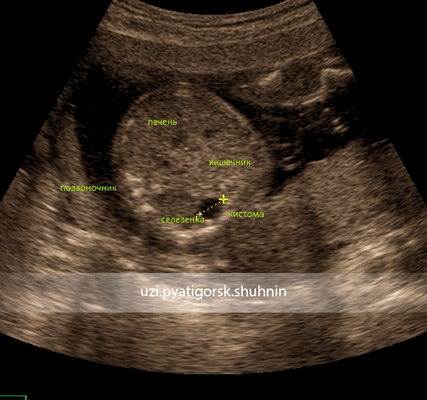

На фото из собственной практики:

УЗИ. Второй скрининг беременности, 18 нед. Киста брюшной полости плода. Особенности расположения кисты позволяют ее расценивать как энтерогенную кисту.